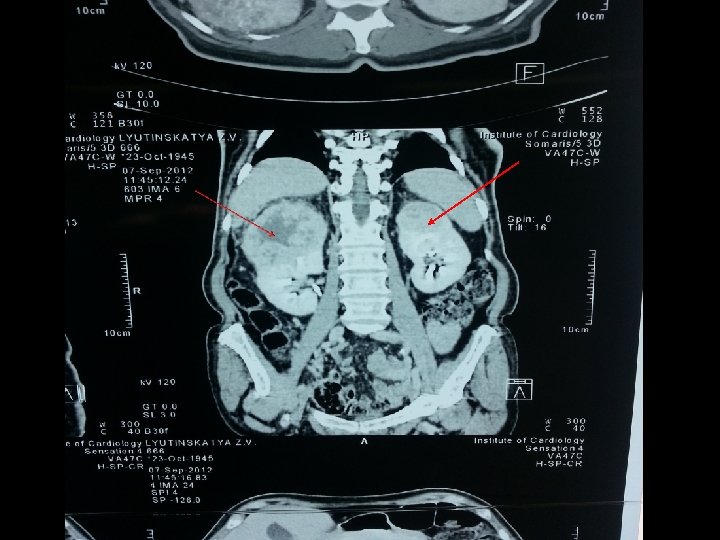

УЗИ • Новообразование левой почки • Новообразование правой почки КТ Обнаружены новообразования в верхних полюсах обеих почек Лимфаденопатии и асцита не выявлено